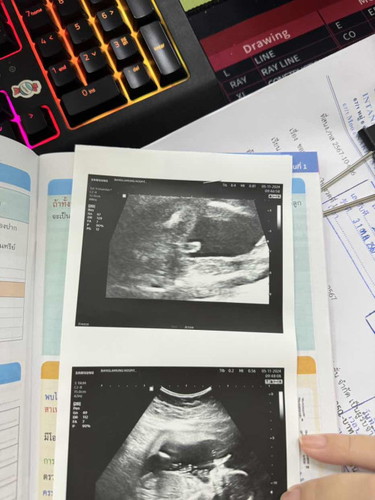

ซาวด์ตอน21wก็โชว์แม่แบบนี้เลย

แม่ๆคะ แบบนี้น้องเป็น ผช แน่ๆใช่มั้ยคะ😊 พอดีญาติฝั่งพ่อกับฝั่งแม่ มีแต่หลานสาวทั้งนั้นเลย

ลูกชายแน่นอนค่ะแม่ ยินดีด้วยค่ะ

ชายค่ะ ชี้มาเลย